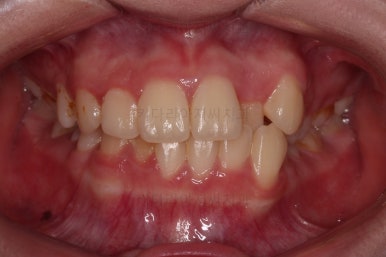

부산교정치료 초진 시 입안의 모습입니다.

치아가 전반적으로 삐뚤고, 덧니가 두드러져 보이네요.

그리고 선을 그려놨는데 윗니의 라인과 아랫니의 라인이 평행이 아니죠.

기울어 있어서 양측의 교합의 강도가 다른 상황이었습니다.